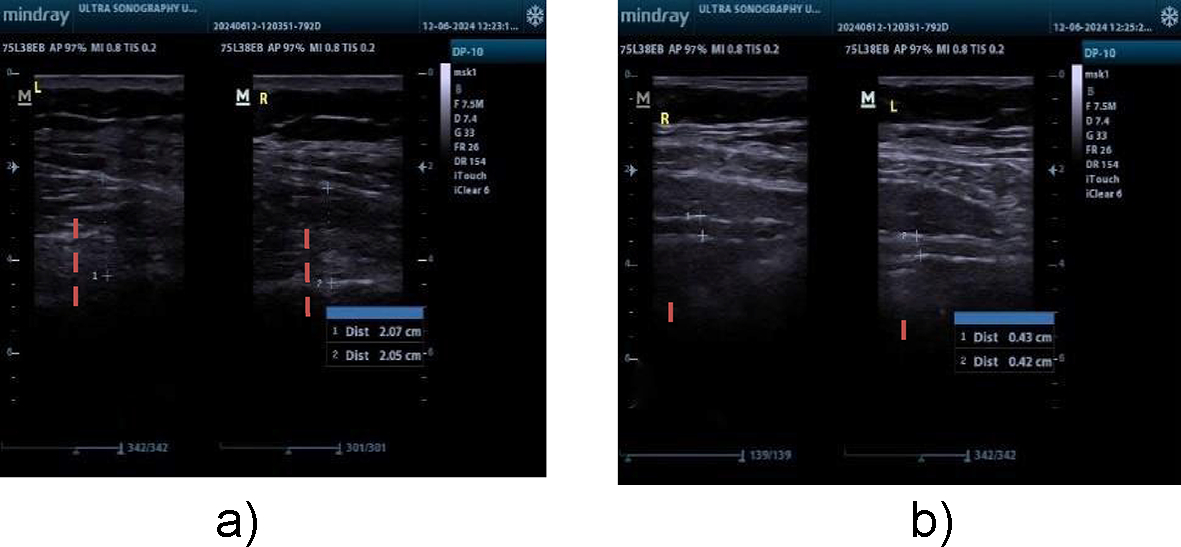

Ultrasonography is a dependable and valid technique with strong intrarater reliability for assessing transverse abdominis and lumbar multifidus muscle thickness in patients with chronic low back pain (CLBP). All measurements of muscle thickness in this research were conducted by one operator, guaranteeing strong interrater reliability. Research has consistently demonstrated elevated ICCs for thickness assessments and contraction ratios in the transversus abdominis and lumbar multifidus muscles under both static (ICC = 0.71–0.99) and semidynamic conditions (ICC = 0.73–0.98)20. Ultrasonography was utilized to assess the LM and TrA muscles. Mindray DP10 ultrasonography was used. For the LM muscle, participants were positioned face down with a cushion under the abdomen to reduce lumbar lordosis. The thickness was measured between the fascial plane separating the muscle from the subcutaneous tissue and the posterior aspect of the L4-5 facet joint21 (Fig. 2a).

r the TrA muscle, a linear ultrasonic transducer was placed horizontally on the abdominal wall at the midpoint between the iliac crest and the lower edge of the rib cage, with its inner edge approximately 10 cm from the midline. The individual was positioned comfortably on their back, with a cushion positioned beneath the knees. The probe was placed with its inner edge approximately 10 cm away from the midline. The probe’s ultimate placement was adjusted to guarantee that the medial edge of the transversus abdominis (TrA) was approximately 2 cm away from the medial edge of the ultrasound image while the participant was in a relaxed position21 (Fig. 2b).

Fig. 2

(a) LM thickness measurement, (b) TRA thickness measurement.